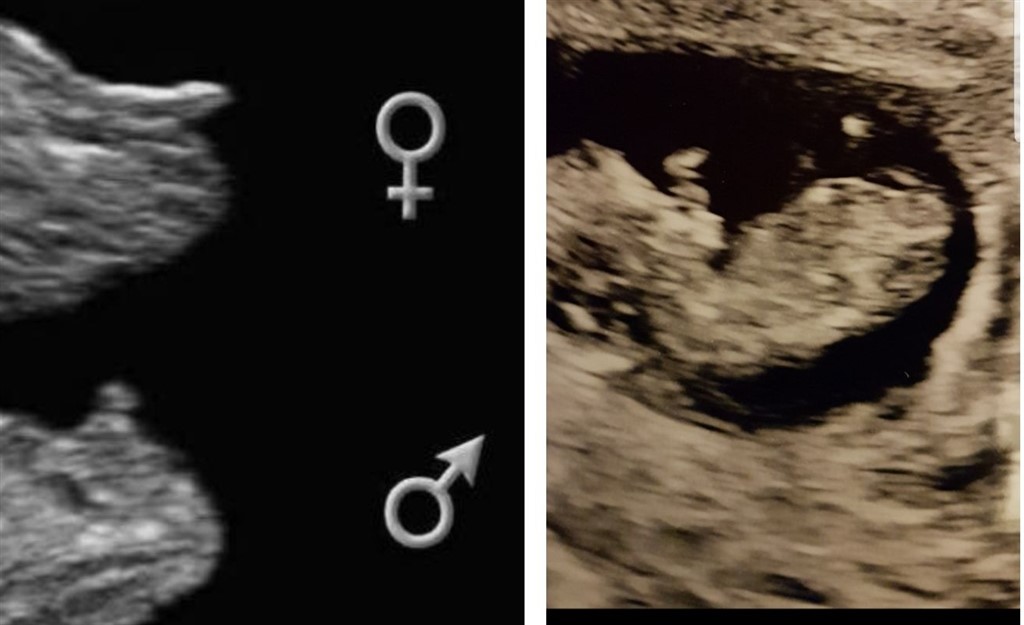

Kan I se hvad køn jeg skal have?

Tænker en lille pige